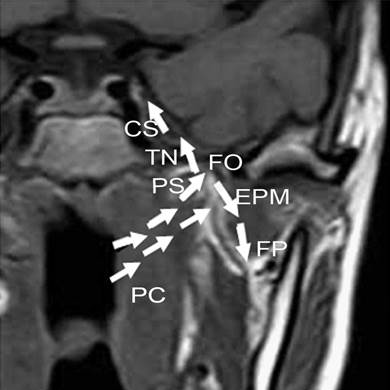

Figure 6

The frist new model for regional invasion of NACC. One regional invasion route was pharyngonasal cavity (PC) → parapharyngeal space (PS) → trigeminal nerve (TN) → foramen ovale (FO) → cavernous sinus (CS), or from parapharyngeal space (PS) → fossa pterygopalatina (FP) → external pterygoid muscle (EPM), as shown with the white arrows.